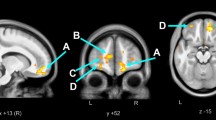

Lastly, we investigated whether the observed association between HIV DNA and global NCI was being driven by specific cognitive domains. In older subjects, higher levels of HIV DNA were significantly associated with worse Executive Functions (p = 0.004), which remained significant after adjusted analysis for EDI (p = 0.01; Fig. 3). No differences were found for any of the other tested domains (all p > 0.10).

Levels of HIV DNA and the Executive Functions domain in older adults.

Comparison of levels of HIV DNA between individuals with normal functioning and NCI in the Executive domain among older adults. Two-sided Mann-Whitney test p values are indicated. Analysis was repeated for while controlling for EDI (in brackets).

On the other hand, we found that older adults with higher levels of HIV DNA presented more severe NCI, particularly in the domain of executive functions (e.g., cognitive flexibility, planning). This effect was not evident in the younger HIV-infected population, despite similar levels of HIV DNA, neurocognitive functioning and cognitive reserve (i.e. years of education and verbal IQ) between age groups. This difference could be a consequence of enhanced transmigration of activated HIV-infected cells through the blood brain barrier, resulting in CNS inflammation, oxidative stress and neuronal injury27,28 and deserves further investigation.